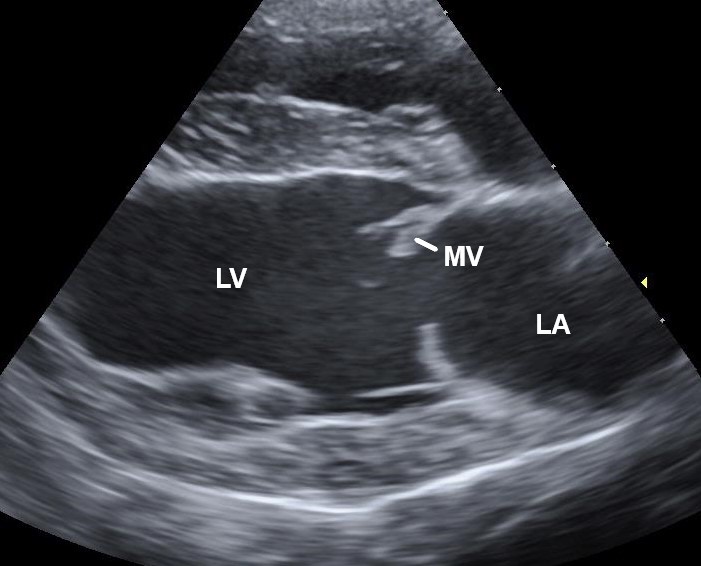

Herzultraschall (Echokardiographie)

Der Herzultraschall, auch Echokardiographie genannt, ist eine schmerzfreie und nicht-invasive Untersuchung, bei der Schallwellen verwendet werden, um Bilder des Herzens zu erzeugen. Diese Untersuchung ermöglicht es, die Struktur und Funktion des Herzens genau zu betrachten und Erkrankungen frühzeitig zu erkennen.